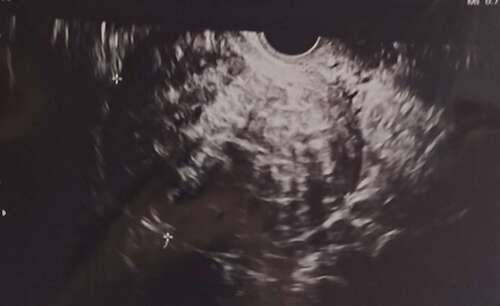

Hierbij de foto van de mijne! Maandag doormiddel van een vaginale echo vastgelegd. Echt een joekel van een ding, sinds zwangerschap verdubbeld in formaat.

Hij zit bovenop mijn baarmoeder en drukt deze in retroflex, waardoor alle druk op mijn darmen is.

Ik snap overigens niet waarom mijn gyenacoloog zegt dat hij in achterwand zit terwijl hij aan de voorkant zit waar mijn buik is?